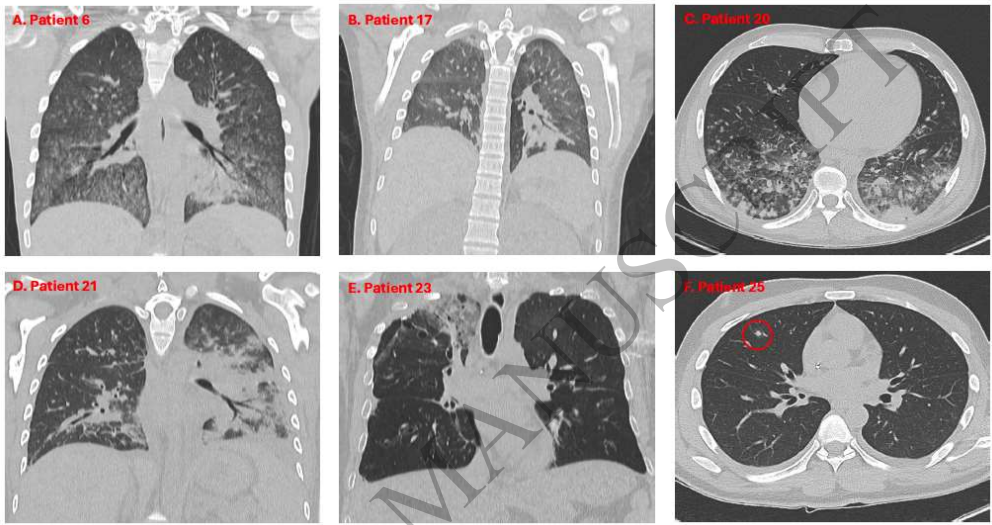

【临床表现】74.2%患者以发热为首发症状,但器官特异性症状隐匿——67%肺病患者无呼吸道症状,69% CNS病变者无神经系统表现。影像学显示:8例多灶性脑病变,5例肺部亚厘米结节(